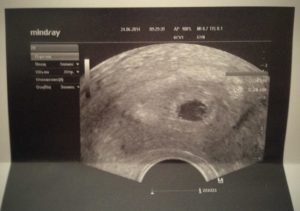

- На 21 день после переноса эмбрионов врач уже может увидеть плодное яйцо, диагностировать благополучную беременность.

- Появляется возможность заметить, сколько эмбрионов прижилось, нет ли внематочной беременности, где ребенок закрепился.

- Иногда врачи назначают ультразвуковое исследование на 6 неделе, что обусловлено жизнеспособностью плода. К сожалению, не всегда первое ЭКО заканчивается беременностью. Но с каждой новой попыткой шансы женщины растут. К 6 неделе после пересадки есть возможность отчетливо услышать, как бьется сердце плода.

Первое УЗИ после ЭКО назначают на 21 – 28 сутки после экстракорпорального оплодотворения. Это стандартная процедура диагностики, позволяющая обнаружить не только беременность, но и положение ребенка, состояние организма будущей матери.